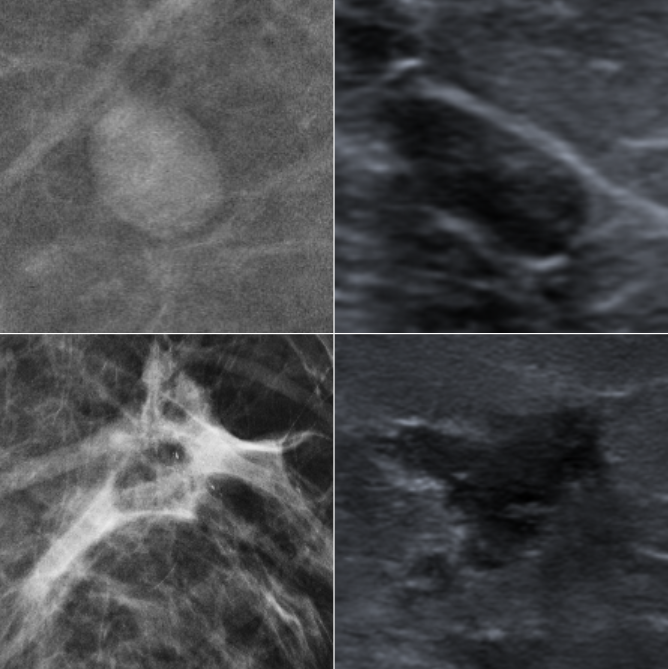

Classification of breast lesions is a challenging task for the radiologist. Malignant and benign lesions can be differentiated by their shape, boundary and texture. For example, malignant lesions may have irregular and not well defined boundaries as they have the ability to spread (see Figure 1). Nevertheless, in many cases radiologists cannot classify the lesion and the patient is referred for a biopsy which is a stressful and expensive process. Given that 65%-85% of the biopsies turns out to be benign [8], there is a clear need for tools that will help radiologists reduce benign biopsies.

Refer to caption

Figure 1: Benign (Top) and Malignant (Bottom) lesions from our dataset. Malignant lesions tend to have less strict boundaries in both mammography (left) and ultrasound (right) screenings.